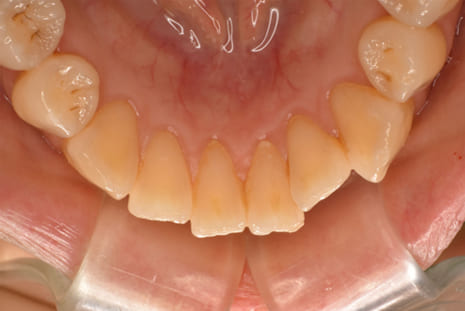

マウスピース矯正装置にて上下顎の矯正を行いました。

足りないスペースは側方への歯列拡大とIPR(歯の間の削り込み)を行い矯正しました。